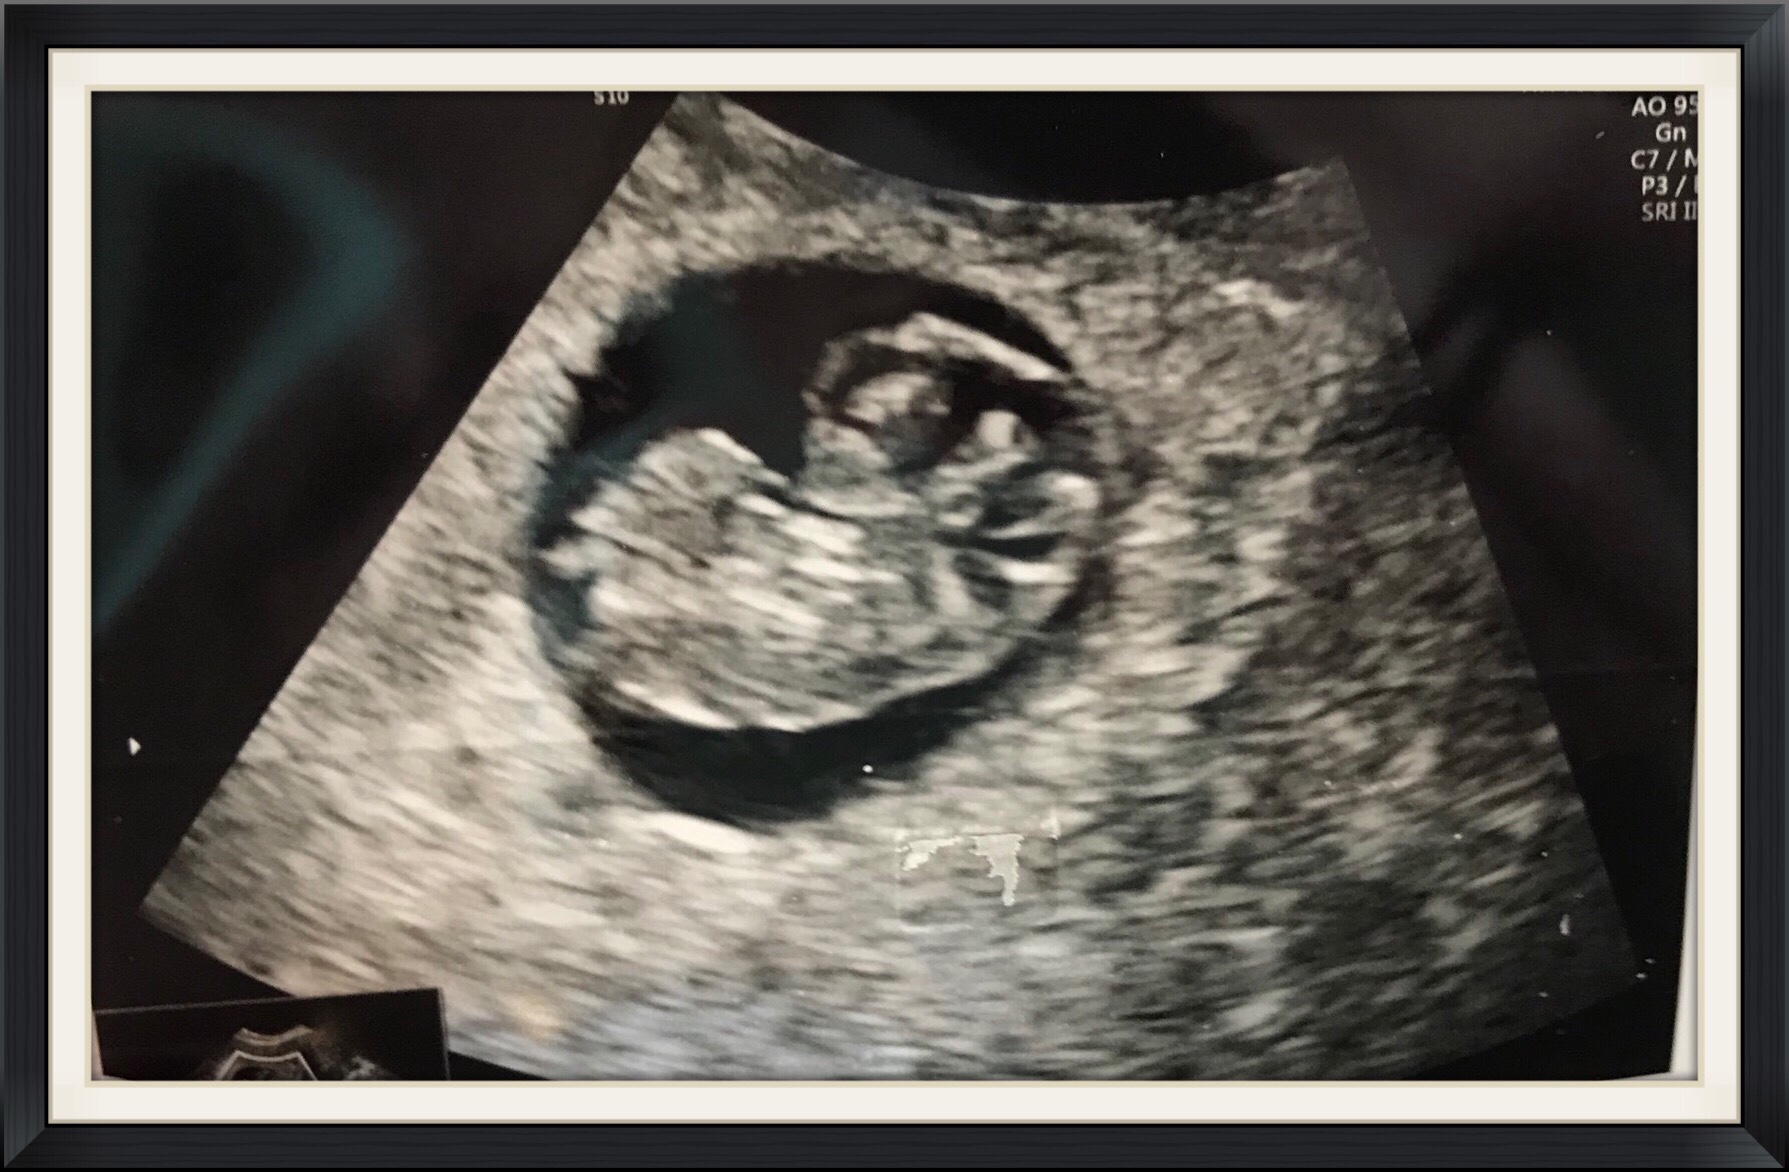

As the blizzard poured down around me I looked out the window and remembered that the doctor said Snow Pea’s results would be in on Friday. Friday went without word, so I logged in to my online chart, “1 new message” it said. I held my breath, my heart raced, I knew what the message was. It was the answer, the answer that Jay and I had been waiting for. It took a while for the words to sink in, “normal (46 chromosomes) XY.”